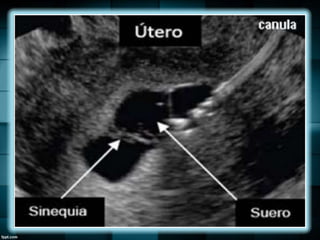

ADHERENCIAS ENDOMETRIALES

(SINEQUIAS)

Causa de infertilidad o fracaso recurrente

del embarazo.

Su pueden observar irregularidades o

bandas hipoecogénicas con forma de

puente dentro del endometrio.

Se ve en forma óptima durante la fase

secretora.

ADHERENCIAS ENDOMETRIALES (SINEQUIAS) Causa deinfertilidad o fracaso recurrente del embarazo. Su pueden observar irregularidades o bandas hipoecogénicas con forma de puente dentro del endometrio. Se ve en forma óptima durante la fase secretora.